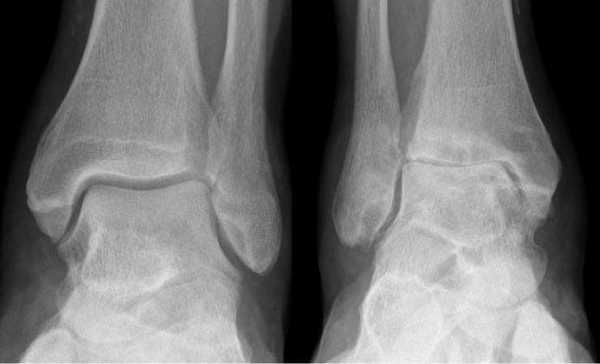

Для подтверждения механической нестабильности выполнены стресс-рентгенограммы голеностопного сустава с «варус-стресс тестом» и «тестом переднего выдвижного ящика». Критериями для постановки диагноза нестабильности является ангуляция таранной кости в коронарной плоскости более 4 градусов и смещение таранной кости кпереди в сагиттальной плоскости на 4 мм, или разница с контрлатеральной стороной в 2 градуса и 2 мм соответственно.

Если с варус-стресс тестом всё очень наглядно, оценивать передний выдвижной ящик рентгенологически чуть сложнее. Для этого можно либо обозначить центр купола таранной кости и встречной суставной поверхности большеберцовой кости точками и сравнивать расстояние между ними с или без нагрузки в задне-переднем направлении, либо использовать в качестве вспомогательного ориентира тень медиальной лодыжки и расстояние от неё до начала шейки таранной кости.

Остеоартроз левого(справа на снимке) голеностопного сустава